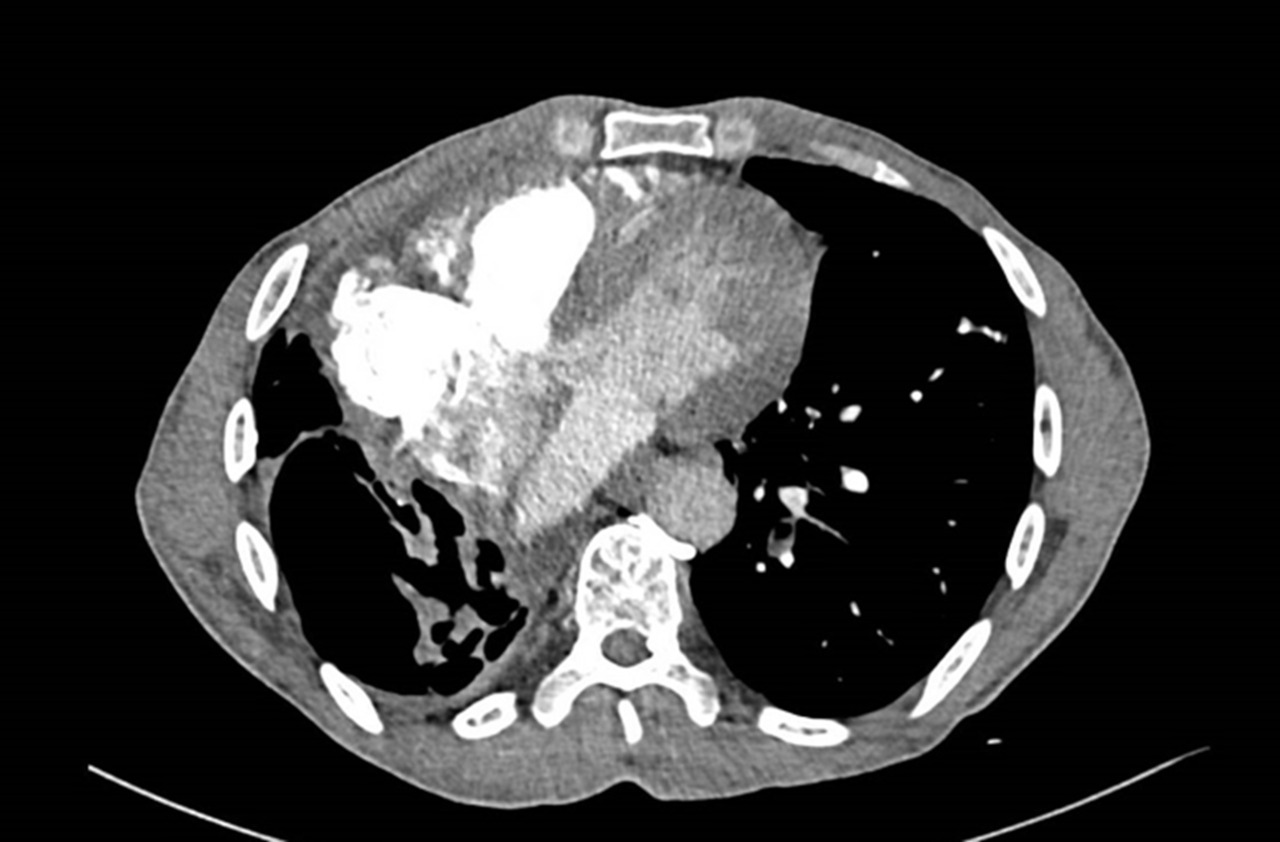

Vous êtes interne de garde aux urgences. Un patient de 71 ans est adressé par son médecin traitant pour dyspnée aiguë.

À l’arrivée, les constantes du patient sont : pression artérielle (PA) = 167/119 mmHg ; fréquence cardiaque (FC) = 114/min ; température (T) = 37,2 °C ; saturation en oxygène (SpO2) = 82 % en air ambiant ; fréquence respiratoire (FR) 30/min.